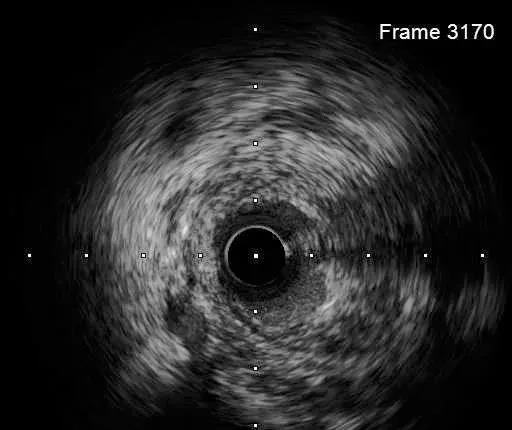

IVUS-2 预扩张后小夹层和血肿

Dia开口

Dia近段

LAD闭塞段

LAD近段

LAD开口